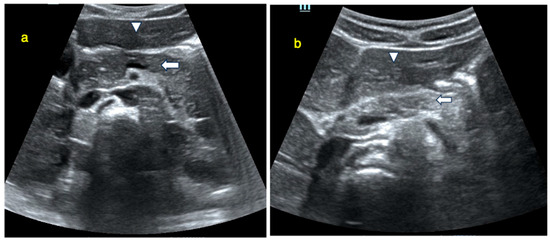

2.2. Pancreas Ultrasonography: Pancreatic Size and Echogenicity